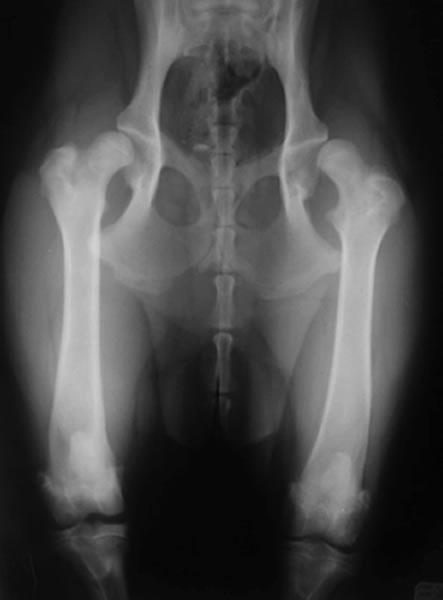

股関節形成不全症

股関節形成不全症とは

成長過程で股関節(寛骨と大腿骨)の発育異常が生じ、股関節に緩みが引き起こされる疾患です。緩みのある不安定な股関節を動かすことで、関節の軟骨部分が損傷を受け関節炎がはじまります。関節炎による痛みから跛行を呈します。

診断

触診、レントゲン検査